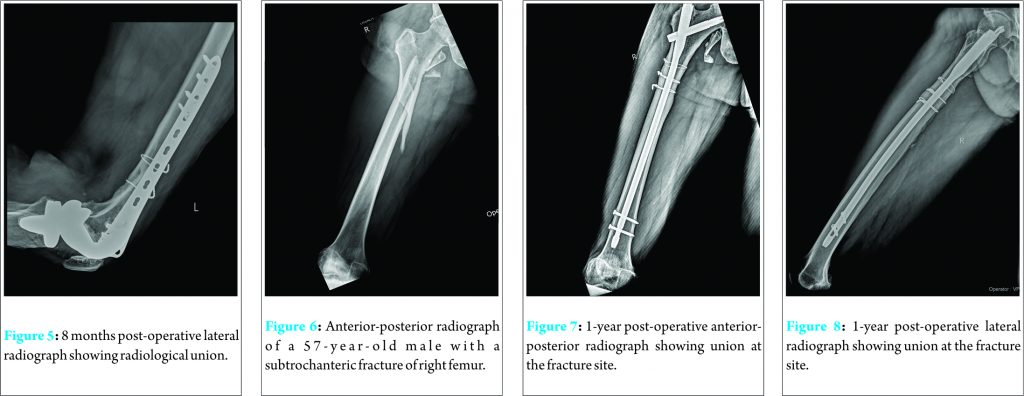

Minimally invasive cerclage technique and instrumentation do not damage the blood supply as there is minimal soft tissue dissection. Moreover, the blood vessels reach the bone primarily in a centripetal direction resulting in minimal disruption by cerclage wiring around the bone [3]. Cerclage wiring provides additional stability to the reduced fracture through centripetal force [3]. Management of periprosthetic femoral fractures can be quite challenging [10]. Cerclage wires are especially useful in stabilizing the proximal femoral fracture after stem insertion in total hip arthroplasty [11]. Cerclage wiring is particularly useful where surgeon faces difficulty for screw placement in periprosthetic fractures, and they provide satisfactory outcomes when used for fixation of periprosthetic femoral fractures. Blocking of the intramedullary canal by prosthesis makes it difficult to use a screw with bicortical purchase [12]. The wires do not interfere with fixation or obstruct the intramedullary canal [3,11,13]. In our case series, three patients had periprosthetic fractures. All cases of periprosthetic fracture were treated with cerclage wiring and plating and resulted in excellent outcome with the union without any complication or need for revision surgery (Fig. 2, 3, 4, 5).

The limitation of extensive surgical handling for passing the wires can be minimized or avoided by using principles of minimally invasive procedure which may improve the clinical utility of cerclage wiring [10]. In this regard, the cerclage passing instrument can be of great help for direct fracture reduction. The newer instruments can allow passage of the wire through a small incision (2-3 cm) resulting in less disruption of blood supply compared to an open wiring method. A cadaveric study has shown that percutaneous cerclage wiring results in minimal disruption of the femoral blood supply [2]. Subtrochanteric femur fractures also pose a challenge for management due to their anatomical and biomechanical features [14]. Fracture malalignment and nonunion are common concerns after the treatment of subtrochanteric fractures with intramedullary nailing [5]. Cerclage wiring is an option for the treatment of such cases. It can assist and maintain a reduction in subtrochanteric fractures and complement intramedullary or extramedullary fixation resulting in a better outcome [5]. In our series, subtrochanteric fractures were the most common indication for the use of cerclage wiring. Cerclage wires helped achieve stable near anatomical reduction which was then augmented with a cephalomedullary nail or plate. We used a combination of cephalomedullary nail and cerclage wiring in three out of five cases while in the other two, it was used in conjunction with 95° blade plate. Union was seen in all cases without any complications (Fig. 6, 7, 8). Titanium locking plates and stainless steel cerclage wires have been successfully used in minimally invasive closed reduction and internal fixation of femoral fractures without any adverse impact on fracture healing [1]. Our results are in accordance with these findings. Stainless steel cerclage wires are preferred in the clinical practice due to their biomechanical characteristics, ease of use and reliability for internal fixation with good stability [14,16,17]. Minimal invasive technique used to pass wires achieves rotational, sagittal and coronal alignment after which the fracture is spanned with either a plate which may be passed submuscularly or an intramedullary nail. A study by Han et al. evaluated the number of wires required for the management of proximal femur fracture in cementless total hip arthroplasty. In this study, three wires were needed to achieve stability [18]. In a comparative experimental study, Lenz et al. [9] have shown that double looped wires perform significantly better in terms of providing fixation stability compared with single looped wires. Thus, multiple wires provide better strength for reduction and maintenance of fracture compared to a single wire. A study has shown that cerclage wire or cable provides excellent mid- to long-term results in the management of intraoperative fracture associated with cementless, tapered femoral prosthesis [14]. Average number of wires used in our study was 2.10 ± 0.70. In our series, intertrochanteric fractures were fixed with a single wire each, while two wires were used in the diaphyseal fracture (Fig. 9, 10, 11). Of the five subtrochanteric fractures, three were fixed with two wires while the other two cases were stabilized with three wires each. Two of the periprosthetic fractures were fixed with two wires each while the third case had three cerclage wires. Our results suggest that the use of cerclage wiring in combination with standard fixation techniques helps achieve primary near anatomical stable alignment and therefore facilitates fracture healing with no significant complications. Minimally invasive procedure and instrumentation preserve soft tissue attachments thus preserving the vascular supply to the involved bone segment [2,3]. The results of our study are significant in light of the limited literature on the use of cerclage wiring in femoral fractures in Indian patients [7,8]. We believe that cerclage wiring can be used as a substitute for interfragmentary screw fixation which requires extensive soft tissue dissection. This should, however, be confirmed with a double-blinded, randomized comparative study. Our study has some limitations. First, this is a retrospective study with limited sample size. Second, there was no control arm to compare the outcomes of the procedure with other techniques. Larger comparative studies are required to confirm the observations from our case series.